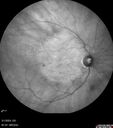

84 year old female The patient had cardiac stents done a week ago. Her stent was done late in the day. She did not notice anything that night but the next morning she noticed that it looked like there was steam coming out of the vent in the ceiling and like there was moister on the mirror. After that her vision changed to look like there was smoke inside her eye. This is more on the left eye than the right eye. Medical Hx: Influenza Immunization Not Received. Pneumococcal Vaccine Not Received. Diabetes Mellitus. Heart attack (2/23/2024). Hypertension, Systemic. Hyperlipidemia. Surgical Hx: Heart Stent (2/23/2024). Hysterectomy. Systemic Meds: Aspirin 81 mg. linaglitin. Metoprolol. NITROGLYCERIN. Ticagrelor. VALSARTAN. VA OD: Dcc20/32 Ncc20/200 VA OS: NccJ16 IOP: TP: OD:11 OS:10

reticular-drusen_119305_052424_05.jpg

Reticular pseudodrusen91 views00000